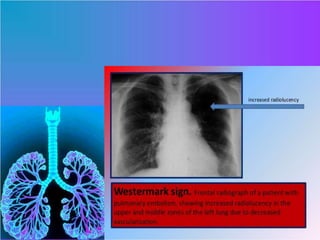

Chest X Ray

• Radiographic signs include:-

• Fleishner sign: enlarged pulmonary artery

(20%)

• Hampton hump: peripheral wedge of

airspace opacity and implies lung

infarction (20%)

• Westermark's sign: regional oligaemia and

highest positive predictive value (10%)

• Pleural effusion (35%)

• Knuckle sign

Ref : http://radiopaedia.org/articles/pulmonary-embolism

DIAGNOSTIC FINDINGS Chest XRay • Radiographic signs include:- • Fleishner sign: enlarged pulmonary artery (20%) • Hampton hump: peripheral wedge of airspace opacity and implies lung infarction (20%) • Westermark's sign: regional oligaemia and highest positive predictive value (10%) • Pleural effusion (35%) • Knuckle sign Ref : http://radiopaedia.org/articles/pulmonary-embolism